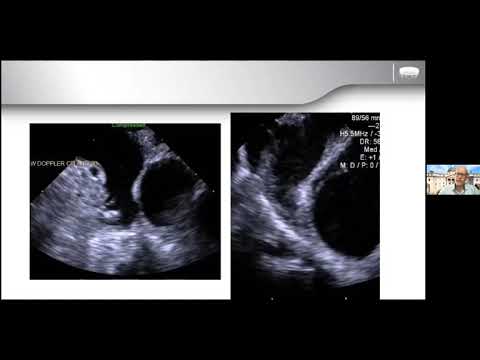

Left atrial appendage closure (LAAC) and Mitraclip